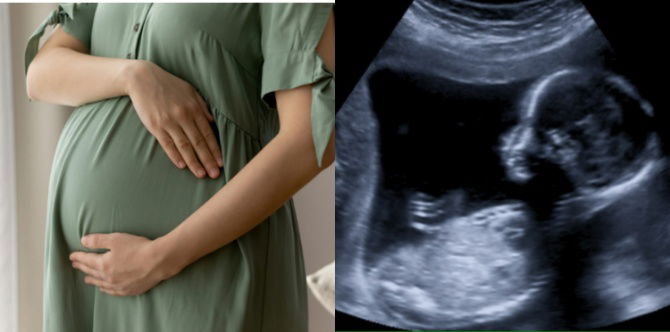

Scan Bayi 16 Minggu Dalam Kandungan

Scan bayi 16 minggu dalam kandungan juga dikenali sebagai imbasan pertengahan kehamilan atau anomali, biasanya dilakukan untuk menilai perkembangan dan kesejahteraan janin.

Imbasan ultrasound ini biasanya lebih terperinci daripada imbasan awal dan memberikan maklumat penting tentang pertumbuhan dan anatomi bayi.

Semasa scan bayi 16 minggu dalam kandungan, ahli sonografi akan:

- Semak Perkembangan Janin: Pakar sonografi akan menilai pertumbuhan bayi, organ, dan perkembangan keseluruhan.

- Sahkan Usia Kehamilan: Scan bayi 16 minggu dapat membantu mengesahkan usia kehamilan dan tarikh jangkaan bersalin.

- Periksa Organ dan Struktur: Scan kandungan boleh mendedahkan maklumat tentang organ bayi, seperti jantung, otak, tulang belakang, buah pinggang dan anggota badan. Ini boleh membantu mengenal pasti sebarang kemungkinan keabnormalan.

- Nilaikan Plasenta dan Cecair Amniotik: Kedudukan dan kesihatan plasenta serta jumlah cecair amniotik akan dinilai.

- Periksa Tali Pusat: Pakar sonografi memeriksa tali pusat untuk memastikan aliran darah yang betul.

- Pengenalan Jantina: Jika anda berminat, dan jika kedudukan bayi mengizinkan, pakar sonograf mungkin dapat menentukan jantina bayi. Walau bagaimanapun, perlu diingat bahawa ini tidak selalunya betul, dan ia bergantung pada kejelasan imej dan kerjasama bayi.

Adalah penting untuk memahami bahawa tujuan utama scan bayi 16 minggu adalah untuk memeriksa kesihatan dan perkembangan bayi, dan ia tidak dilakukan semata-mata untuk mengetahui jantina.